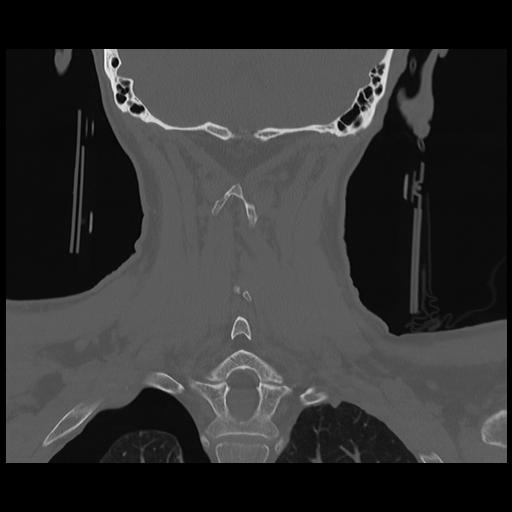

16 HUESO,,Coronal,2.000,HUESO,Coronal,